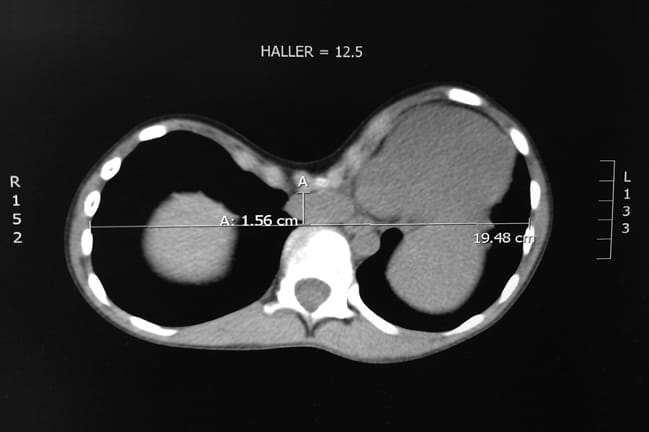

In 2001, Hebra and Robert E. Kelly Jr., M.D., from Children’s Hospital of The King’s Daughters in Virginia developed a ten-year study of 327 pectus surgery patients at 11 medical centers. All were evaluated pre-operatively and one year post-operatively with computed tomography (CT), pulmonary function tests, and body image survey. The CT scans provided the patient’s Haller index, the objective measure of the severity of the deformity; a score greater than 3.2 is considered significant.

The final report, published in the December 2013 Journal of the American College of Surgeons,showed that surgical correction on those patients with a Haller index of 4 or greater improved pulmonary function and total lung capacity. In a smaller subset of patients who underwent testing during exercise (stress test), the investigators were able to demonstrate significant improvement in oxygen delivery by the heart and improved exercise tolerance.

Figure above: CT scan demonstrates compression of the lungs and complete shift of the heart into the left side of the chest. The sternum is almost touching the spine.